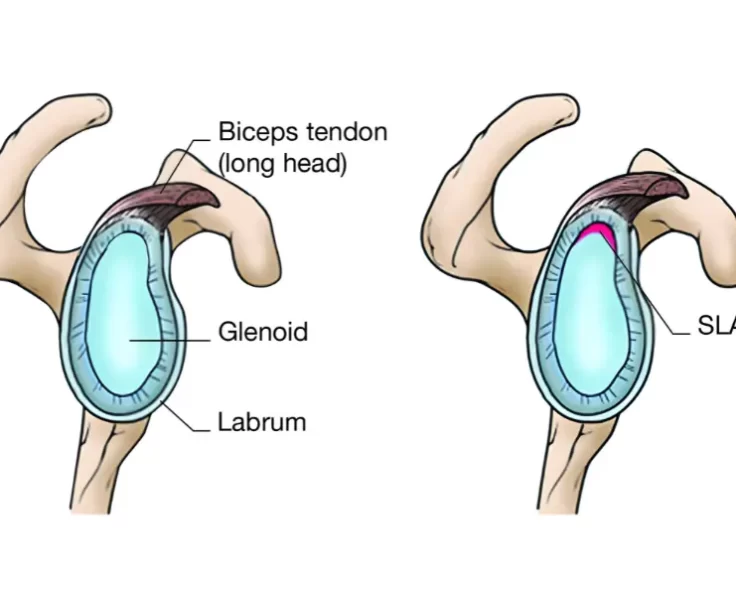

SLAP Repair

The upper arm bone, shoulder blade, and collarbone make up your shoulder joint, which is a ball and socket joint.

Bankart Repair

A Bankart Repair is a treatment that is used to avoid recurrent anterior shoulder dislocations caused by instability in the shoulder's rear.

Posterior Labral Repair

The shoulder joint is a ball-and-socket joint that joins the upper arm's (humerus) bone with the shoulder blade (scapula).